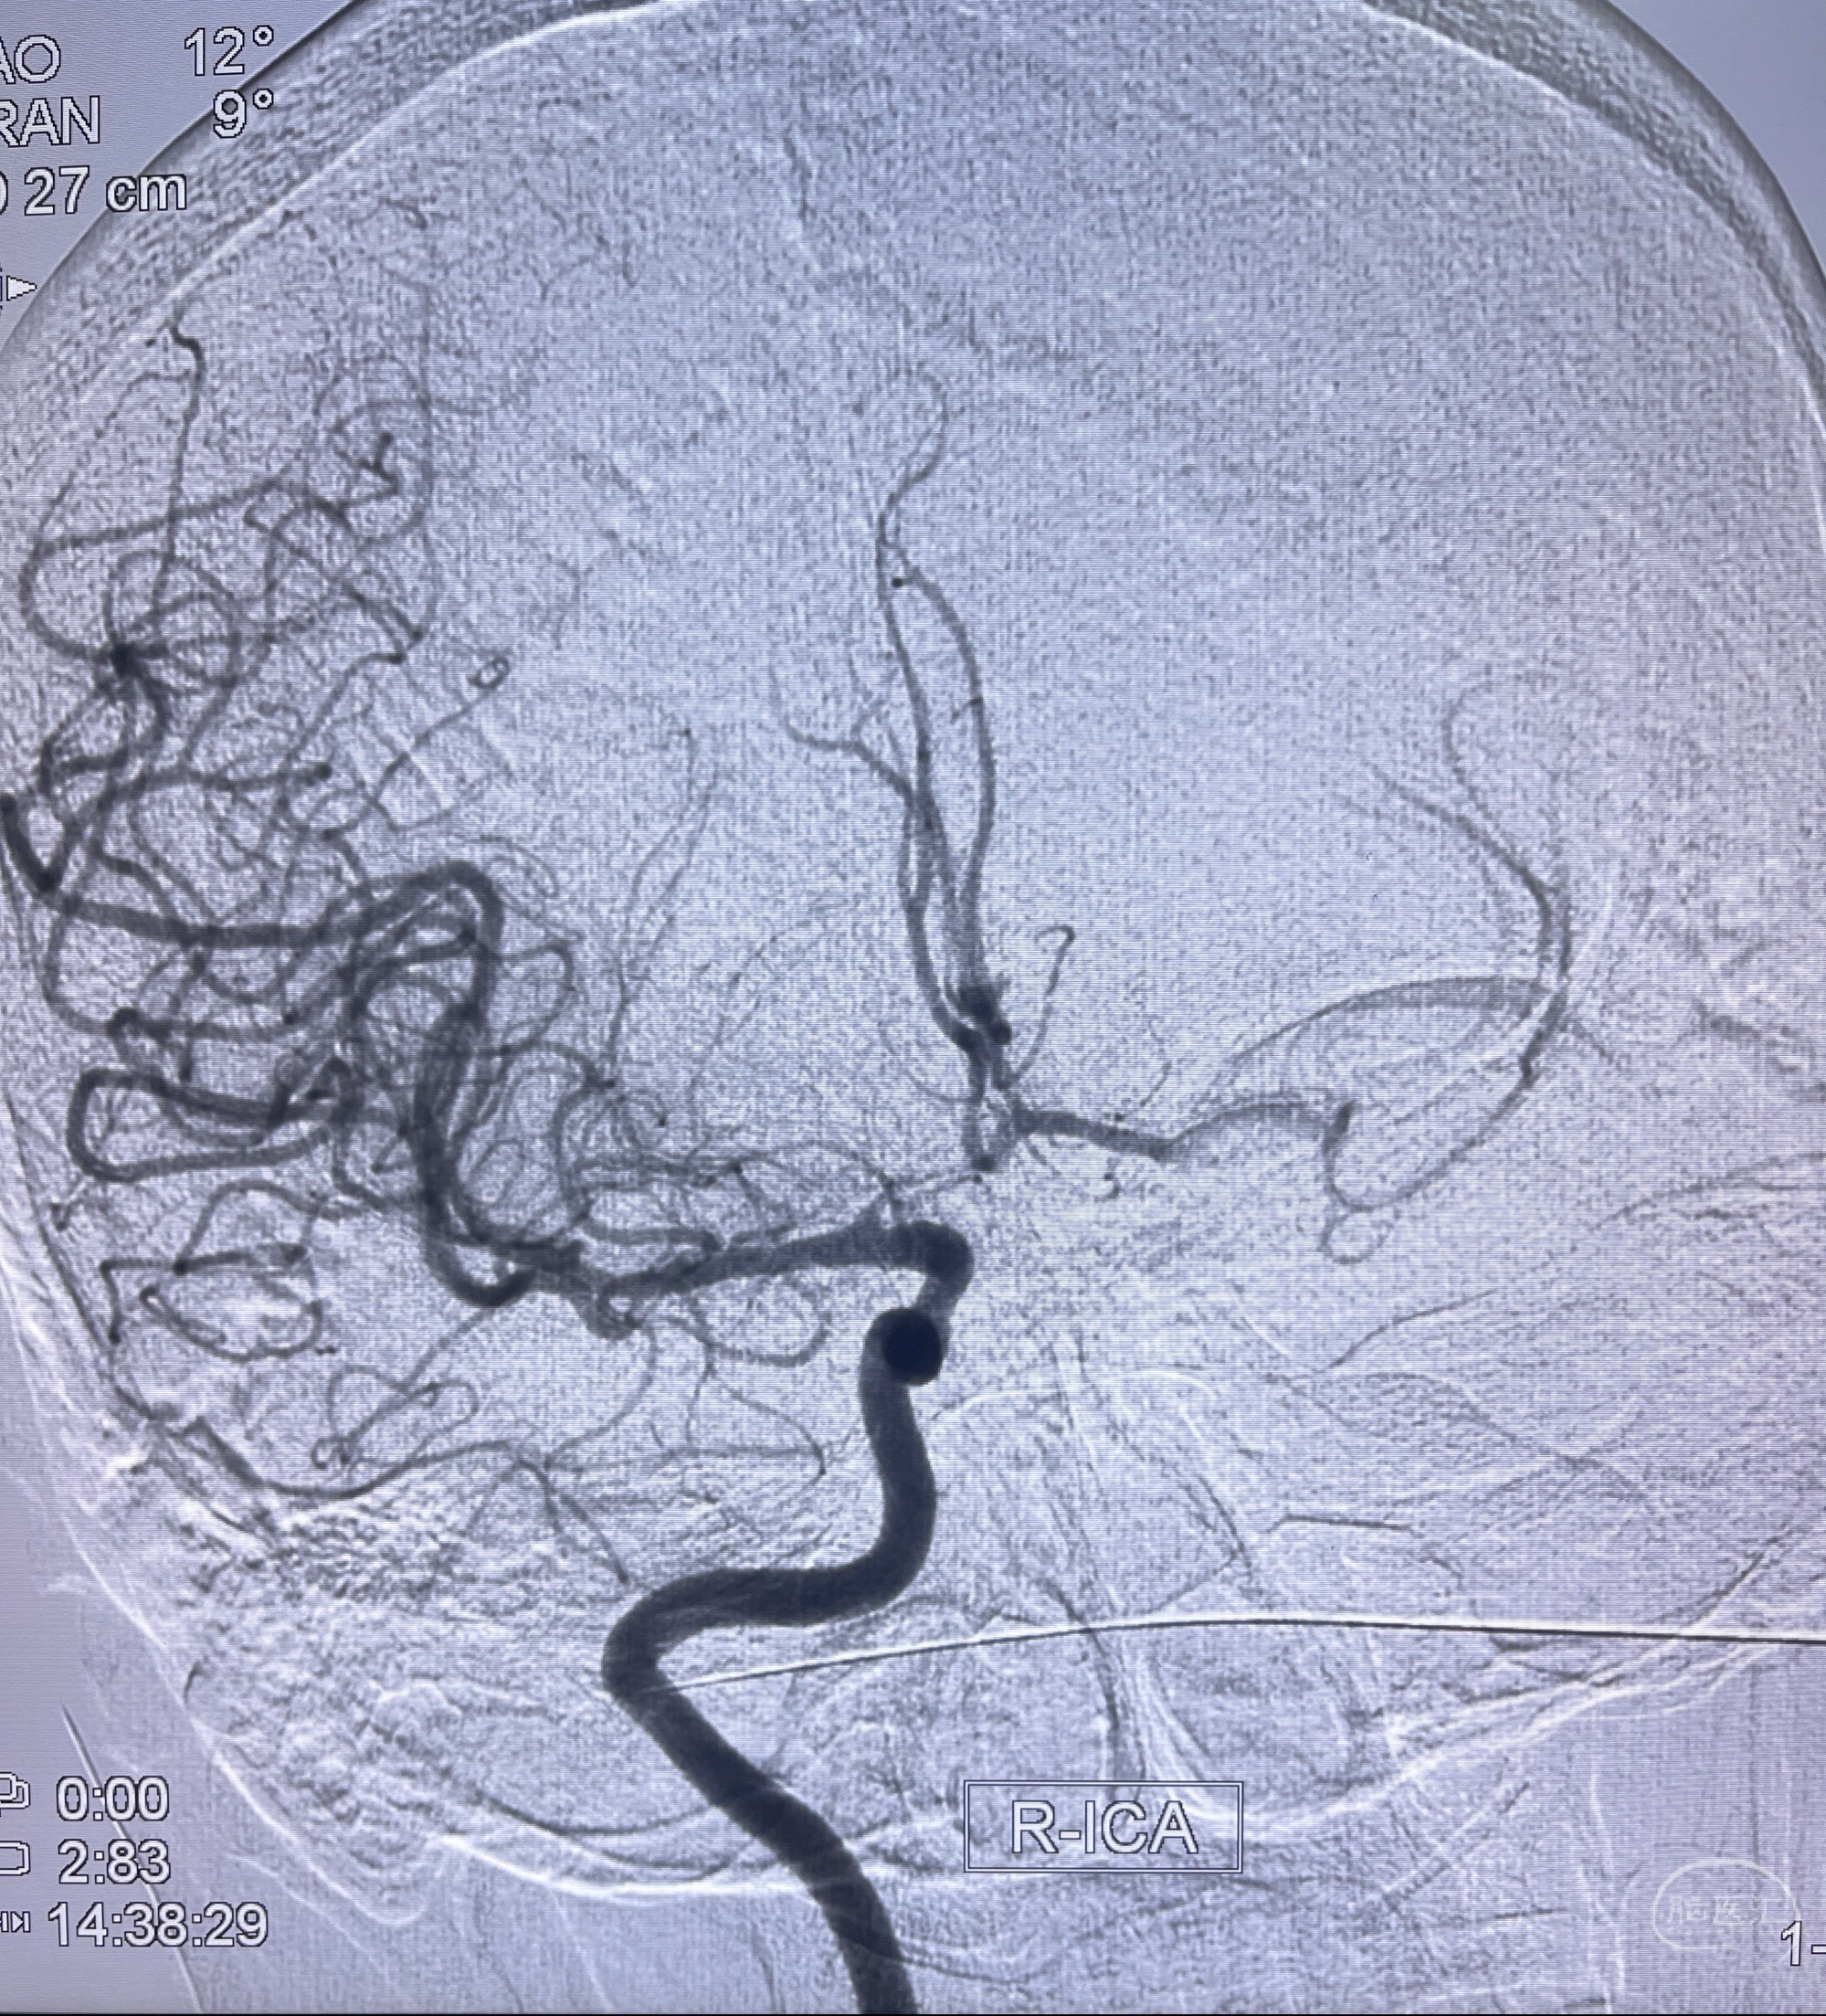

1.左侧大脑前动脉远侧段(A2-A5)动脉瘤

2.双侧颈内动脉狭窄

2023-08-23DSA:左侧前交通动脉瘤,左侧A3/4交界处多发动脉瘤